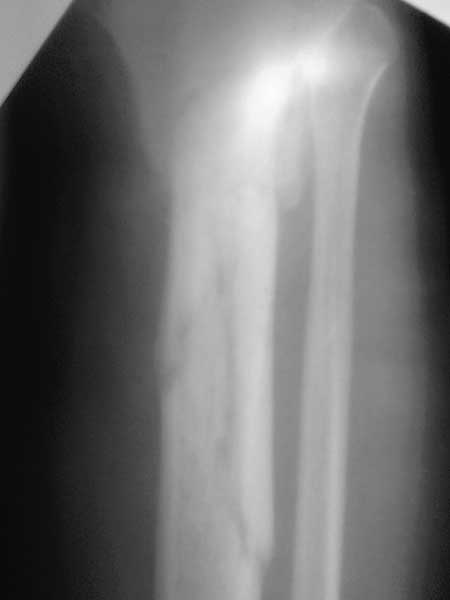

Важны мнения опытных докторов владеющих интрамедуллярным остеосинтезом. Пациент 50 лет.В анамнезе з/оскольч.перелом в/з-с/3 б/б кости. Был в АВФ 9 мес, демонтирован по его словам по поводу спицевой инфекции.также был со слов вскрыт гнойник на передней поверхности голени в зоне ложняка. на данный момент клинически: патол.подвижность в в/з голени и заживающая рана 0,2*4см по передней поверхности голени в зоне ложняка с скудно-умеренным серозным отделяемым( скорее вне зоны проведения спиц). Подвижность -умереннная. Трофических и сосудистых нарушений можно сказать нет. Сгибание в коленном суставе возможно без насилия ок. 50град. Вопрос - как делать? Нам предстваляется два пути: 1.Не дожидаясь заживления раны о/с АВФ,с открыванием ложняка: почистить его+ остеотомия малобрецовой ближе к н/3-с/3 границе. 2.перевязывать рану, после заживления подождать недельки две. Паралельно разрешить приступать на конечность. 2.1Если гной будет то см.вариант1.

Жаль, что нет фасной проекции. Перелом на 2 уровнях, есть искривление костно-мозгового канала. Проксимальный отломок короткий. Вывод: лучше не штифтовать.

3.Перелом на 2 уровнях, есть искривление костно-мозгового канала. Проксимальный отломок короткий.